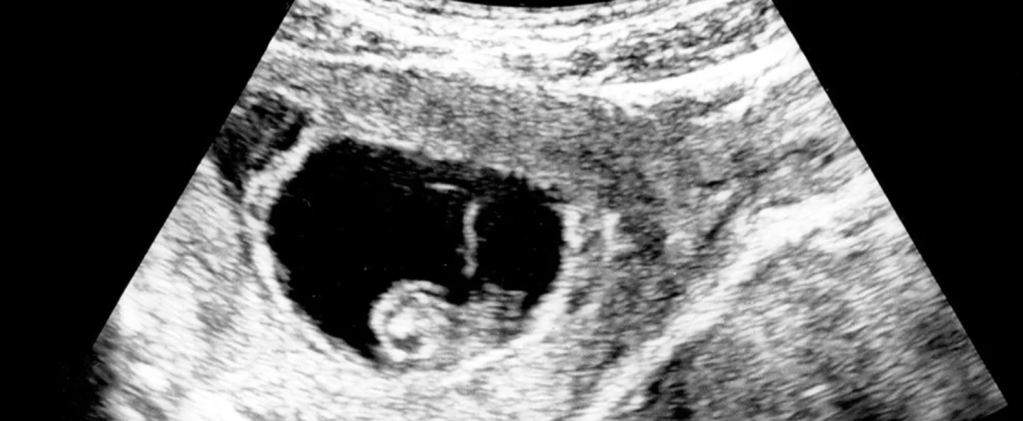

The successful introduction of the “fetal heartbeat” law as a new threshold for access to abortion used the rather illusory cardiac impulses visible on a sonogram introduced in prenatal care as a means to reassure pregnant women of the viability of pregnancy as a means to impose penitent reflection. In Texas, the notorious anti-abortion group in Texas had readily identified Alito as an advocate to staunch a tide of judicial review of restricting access to abortion in Texas and other states, from banning the safest and most widespread abortion procedure after the first trimester or prohibiting abortion beyond seventeen weeks from conception.

The spread of mandated ultrasounds has rather disturbingly grown across the United States as a type of non-medical intervention since 2013. Their effect remains unclear on health care. Even as they have led women seeking abortions to be forced to view and have described to them–whether they desire or not–in states of Texas, Oklahoma, Louisiana, North Carolina and Wisconsin, as an odd interruption of medical care. It is less conclusive relation to women’s change of heart to proceed with an elected procedure. What was imagined as an exercise of biomedical introspection was held up in local courts. Yet the image-making technology able to confirm viability of a pregnancy has now been quite alarmingly high-jacked in Texas as a way to remap the start of personhood in the embryo, in hopes to curtail access to health care in ways that would remap women’s access to reproductive care.

The false objectivity of the promise to “ban abortion from the moment in pregnancy that a heartbeat can be detected” shifts the threshold for legal abortions in many states, claiming to reflect on the “best methods of standard medical practice” to detect “embryonic heartbeat[s] . . . very early in pregnancy, typically by 6-10 weeks gestation.” If transabdominal ultrasounds detect these “heartbeats” by 7-12 weeks, detection of a heartbeat “even earlier than six weeks”–even three weeks from the last menstruation!–seems a revelation of the divine power of creation, and an eery celebration of the proto-human form as alive, in the sense that it seems to have a crude arterial and venous network, and a partitioning into atria and ventricles in a proto-heart, with defined aortic arch arteries, as well as a ventral and dorsal aorta, completed by an often perceptible flutter of cardiac activity, though far from a steady rhythm. But the argument that even the slightest beat is a sign of humanity, led to the crusading call that “to ignore that indicator, the heartbeat is heartless” has put the antiabortion activism on new terrain.

8. The “proof” of personhood that the ultrasound offers is far from a clear “heartbeat” that the law’s name would imply. The elusive and illusory standard of a “fetal heartbeat” uses the cardiac activity in the pre-fetal embryo as a mandated threshold for medical care on the authority of an image, more than medical expertise. It is rather a rejection of medical expertise: if medicine helped to frame the basis for viability outside of the womb that was a standard for determining legal abortions in Roe v Wade, the heartbeat was arrived at as an evasion of medical truth or knowledge, able to reinforce preconceptions of the immorality of abortion: working from the slogan ‘Abortion stops a beating heart,‘ which offered no timeframe, an anti-abortion activist in Ohio tried to reframe the debate about access to abortion to foreground its injustice by directing attention to the “inhumanity of abortion” which has gained new legs on social media: Janet Folger Porter introduced the Ohio Heartbeat Protection Act, one of the strictest restrictions on abortion when it was framed in 2019, in hopes to take the antiabortion fight global, encouraged by the large number of antiabortion judges appointed by Donald Trump who are eager to restrict abortion rights in the nation.

Yet the image of the sonogram is quite hard to detect or to call an index of life. The “now-you-see-it-now-you-don’t” quality of whatever flicker of motion is detectable in a sonogram of a fetal pole is almost illusory; the measurement introduced in prenatal clinical care to reassure women of a pregnancy’s viability is neither a heart beat and in fact impossible to measure,–even if it seems to be about to admitted in court as a grounds for criminalization in a terrifyingly authoritarian manner–but a substitute for the notion of viability borrowed from obstetric care at the heart of Roe v. Wade of twenty to twenty-six weeks of gestation, the threshold for a woman’s constitutional right and limits of viability of the newborn outside the womb, now considered approximately twenty-four weeks.

Only an advanced and invasive ultrasound technology is able to detect what has been called the first flutter, a full month before the embryo is a fetus or even has an organ that is recognizable as a heart.